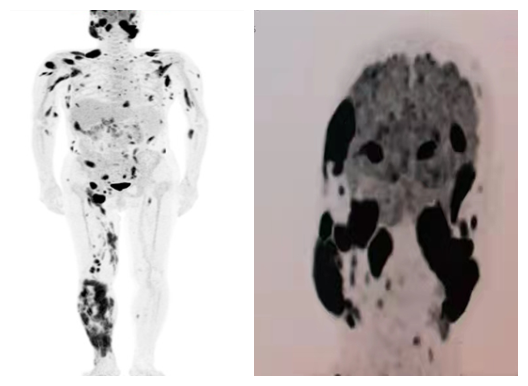

PET-CT检查(2022-02-28):头面部及颌面部多发软组织肿块影,FDG代谢异常增高;体部、双侧上肢及右侧下肢皮下多发软组织结节、肿块(SUVmax=12.6),FDG代谢异常增高;双侧乳腺多发结节样FDG代谢增高灶,FDG代谢异常增高(SUVmax=6.3);双侧颈部、双侧腋窝、肝左叶前方、腹主动脉旁、双侧髂血管旁及双侧腹股沟多枚肿大淋巴结影,FDG代谢异常增高;大网膜增厚,内见多发软组织结节影(SUVmax=14.8),FDG代谢增高。

图1. PET-CT提示患者淋巴结多发和皮下多处结节侵犯,考虑淋巴瘤多发浸润